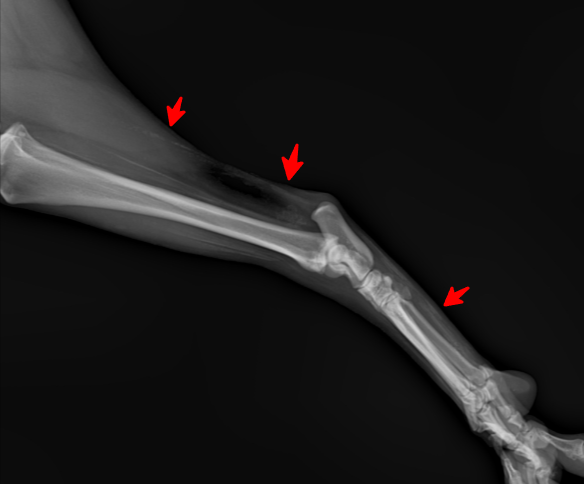

우선 엑스레이 사진상 명확한 비정상적 구조가 보입니다.

화살표로 표시된 부분의 근육 혹은 인대의 석회화 양상이 매우 뚜렷한 양상을 보이고 있고, 이는 양측 후지 모두에서 관찰되는 바 대사성 질환이나 전신성 질환이 있을 가능성이 높고,

화살표 한 부분이 반대쪽에 비해 부종 양상이 명확하게 관찰되기 때문에 근육 및 인대의 석회화를 유발하는 질환 https://diamed.tistory.com/1023 이 원발로 있다가 충격에 의해 인대나 근육이 찢어졌을 가능성이 높다는것을 의미합니다.